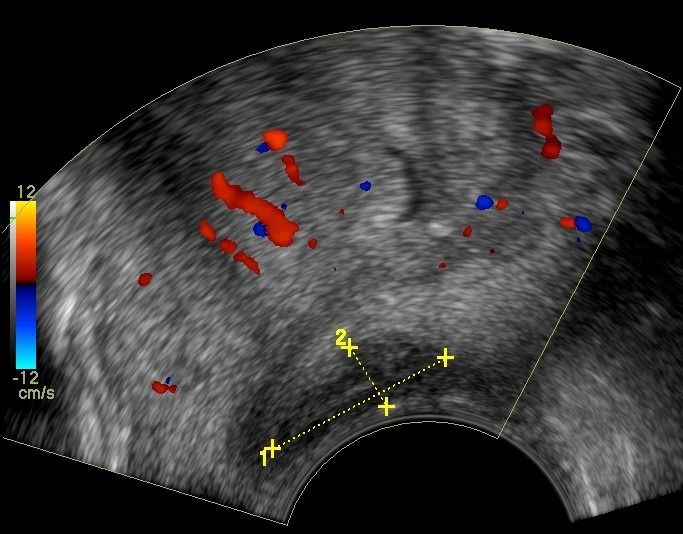

- Peripheral Prostate Zone: The exam can detect focal lesions, such as neoplasms, in the peripheral zone of the prostate.

- Central Prostate Zone: The central zone can be checked for the presence of inflammation, abscesses, calcifications, or other space-occupying lesions.

The Transrectal Ultrasound provides more information about the size, morphology, and focal lesions of the prostate compared to the lower abdominal ultrasound. As a specialized examination, it is performed when there are clinical and biochemical indications, such as elevated PSA (prostate-specific antigen).